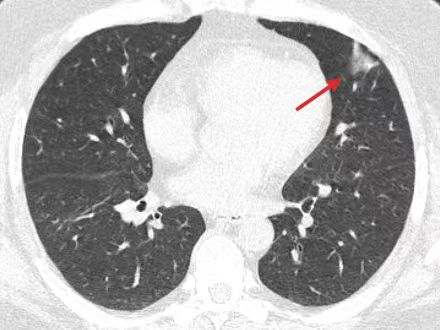

L先生焦急的来到taptap点点在哪注册感染科,关瀛医生接诊后,查指脉氧只有92%,急查血气分析:氧分压62mmHg,严重低氧血症!立即氧疗,加强监护,同时急查胸部CT检查,提示双肺散在斑片浸润影。

抽血提示淋巴细胞百分数53.3%,反应性淋巴细胞10%,ALT 65U/L AST 84U/L,感染性疾病科庄鹏主任查房指示该患者异淋明显升高,有传染性单核细胞增多症样症状,肺部见斑片状磨玻璃影改变,同时肝功异常,需警惕EBV或CMV感染,进一步检查变虽未见EB病毒及其他病原体感染证据,但发现巨细胞病毒IgM抗体阳性,核酸(HCMV-DNA) 1.28E+05!且按肺炎抗感染治但疗3天患者仍有反复发热,考虑患者巨细胞病毒感染。立即予激素、更昔洛韦抗病毒治疗。经过系统治疗,L先生病情很快好转。呼吸感染科联合党支部书记陈小可主任查房,指出患者显著缺氧,胸部CT影像符合病毒性肺炎,未发现其他病原菌,抗病毒治疗有效,考虑并发巨细胞病毒肺炎,

成人巨细胞病毒肺炎与临床常见的细菌性肺炎在症状、体征和影像学检查等方面表现相似,临床难以鉴别,误用抗生素治疗会加重甚至延误病情,本病得不到及时治疗,可继发全身感染甚至并发多脏器衰竭,危及患者生命。